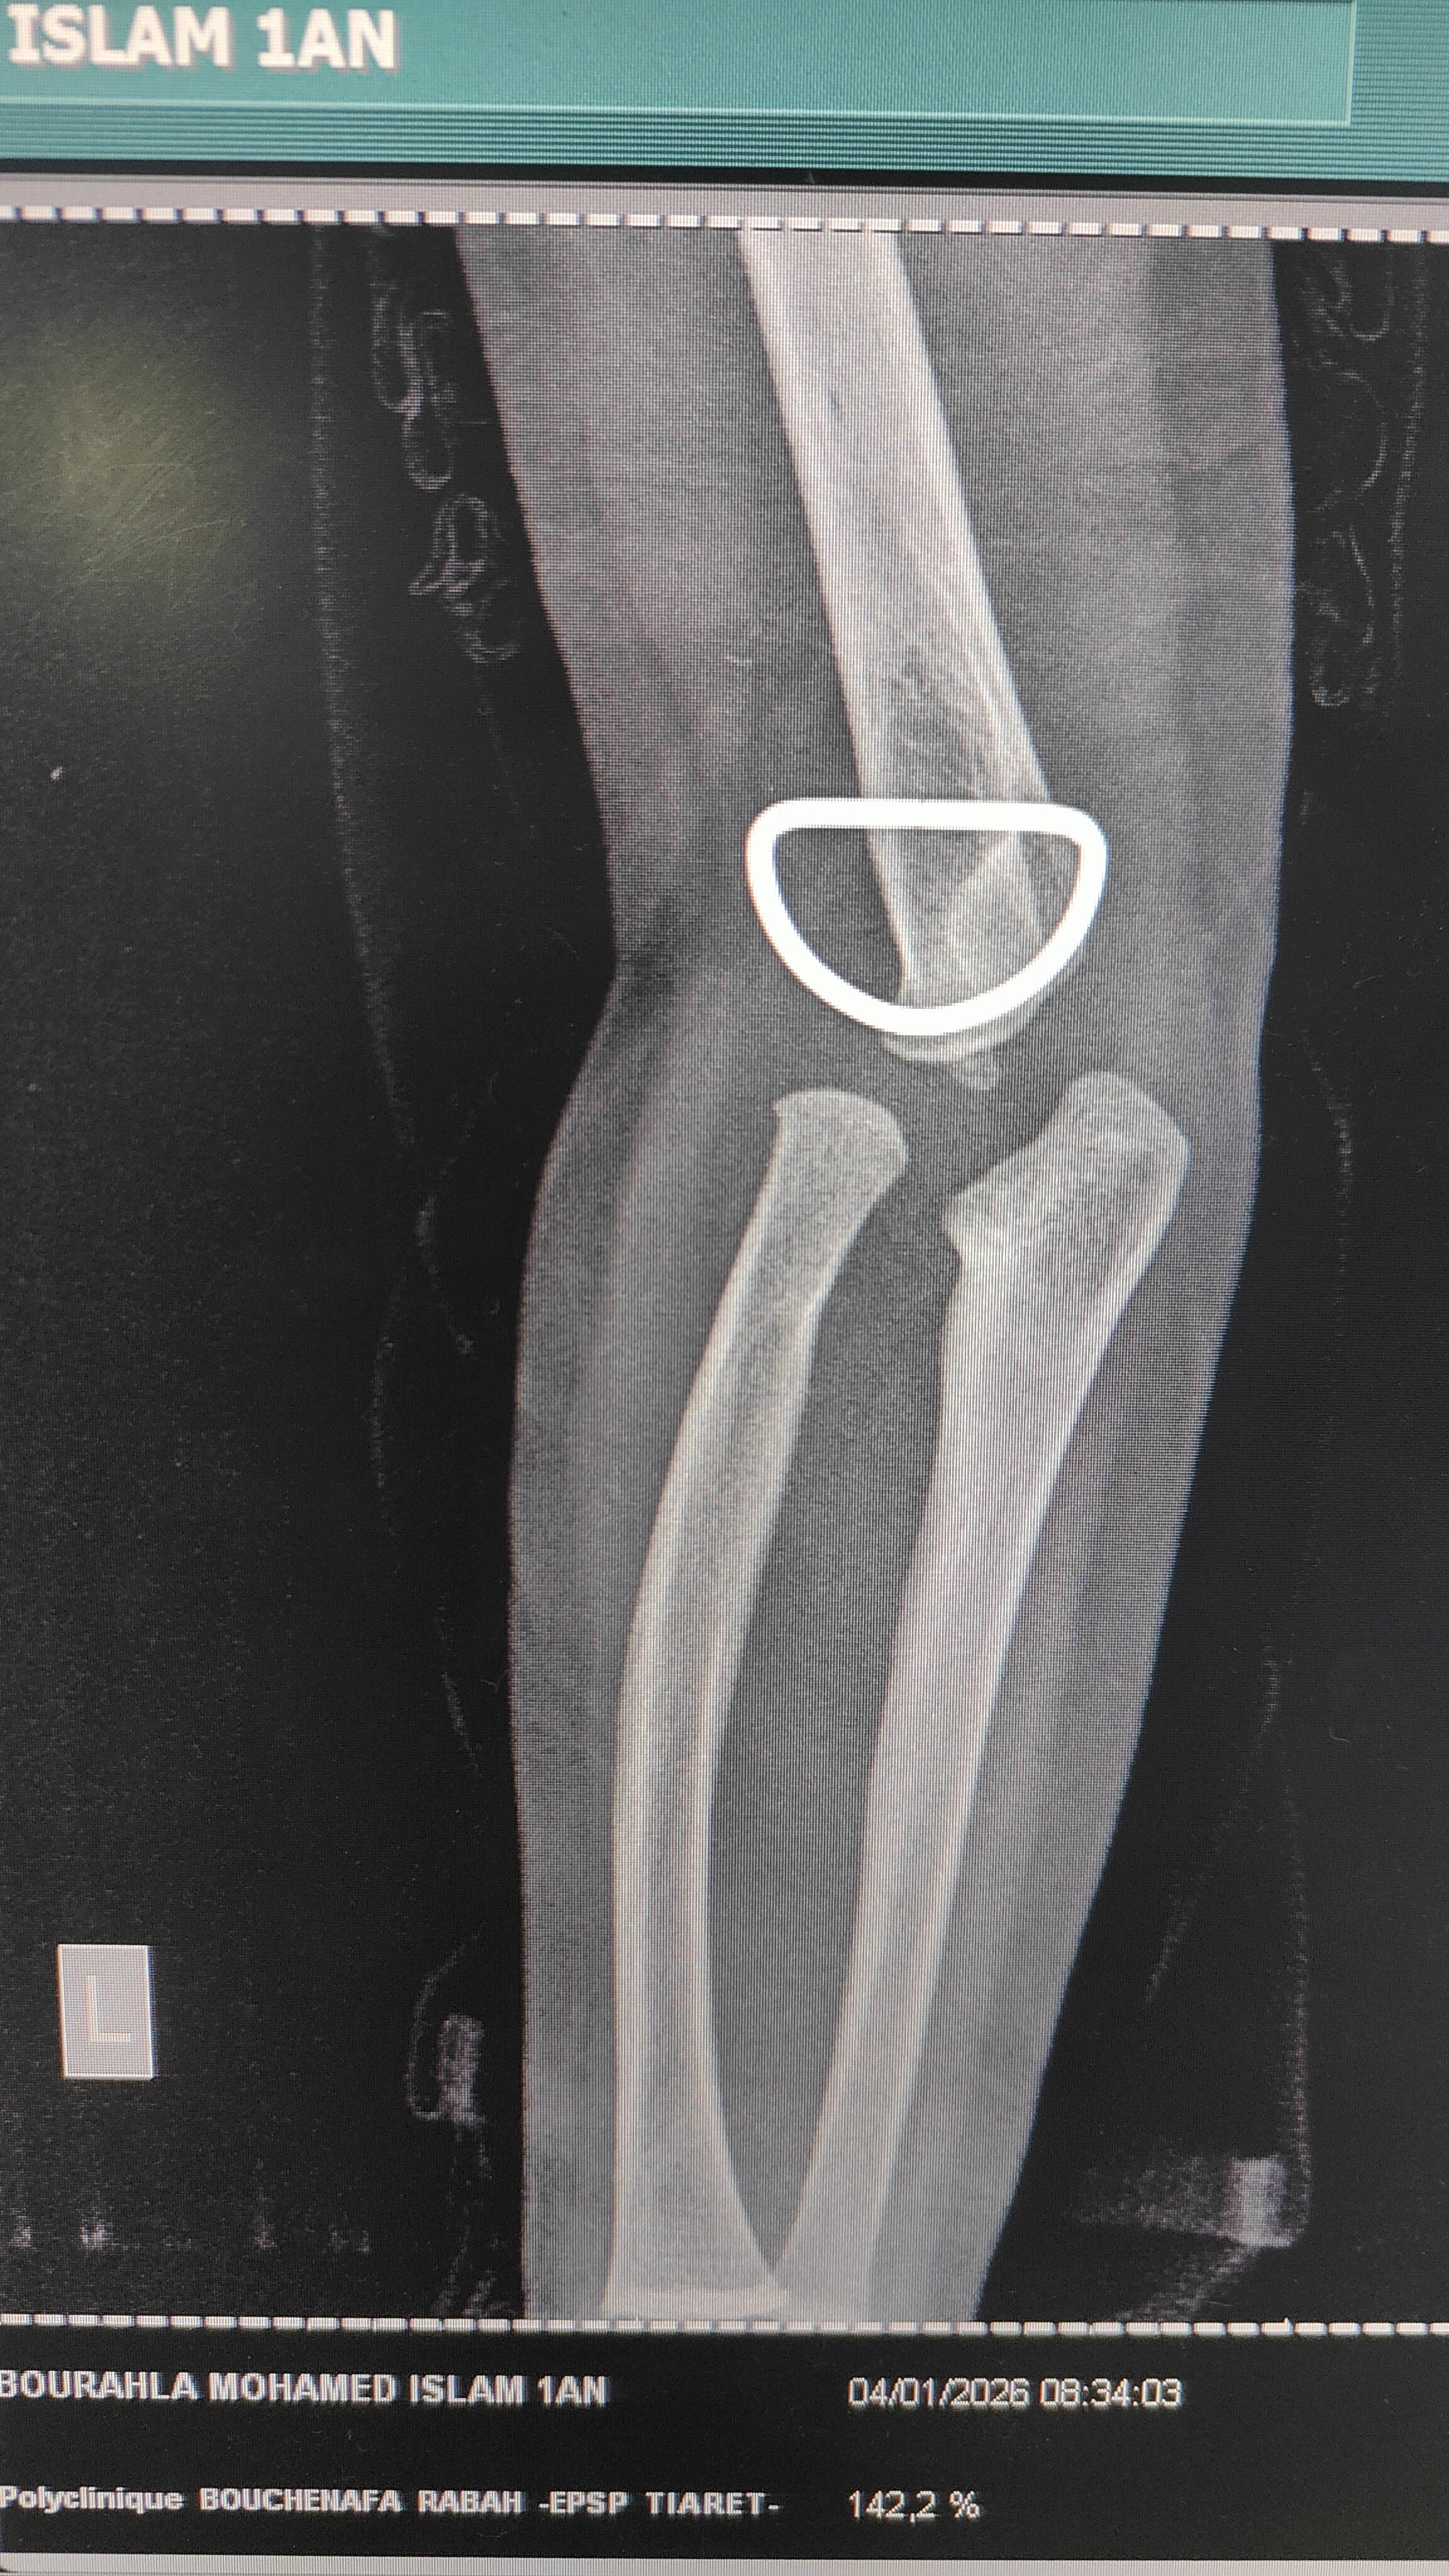

الحالة طفل بسن سنة و6 اشهر منذ الولادة لوحظ انتفاخ في الساعد بالقرب من المرفق ومع مرور الزمن اتضحت صعوبة في دوران اليد يمين يسار ويظهر في اشعة الراديو فراغ عند المرفق يبدو كخلع للعظم